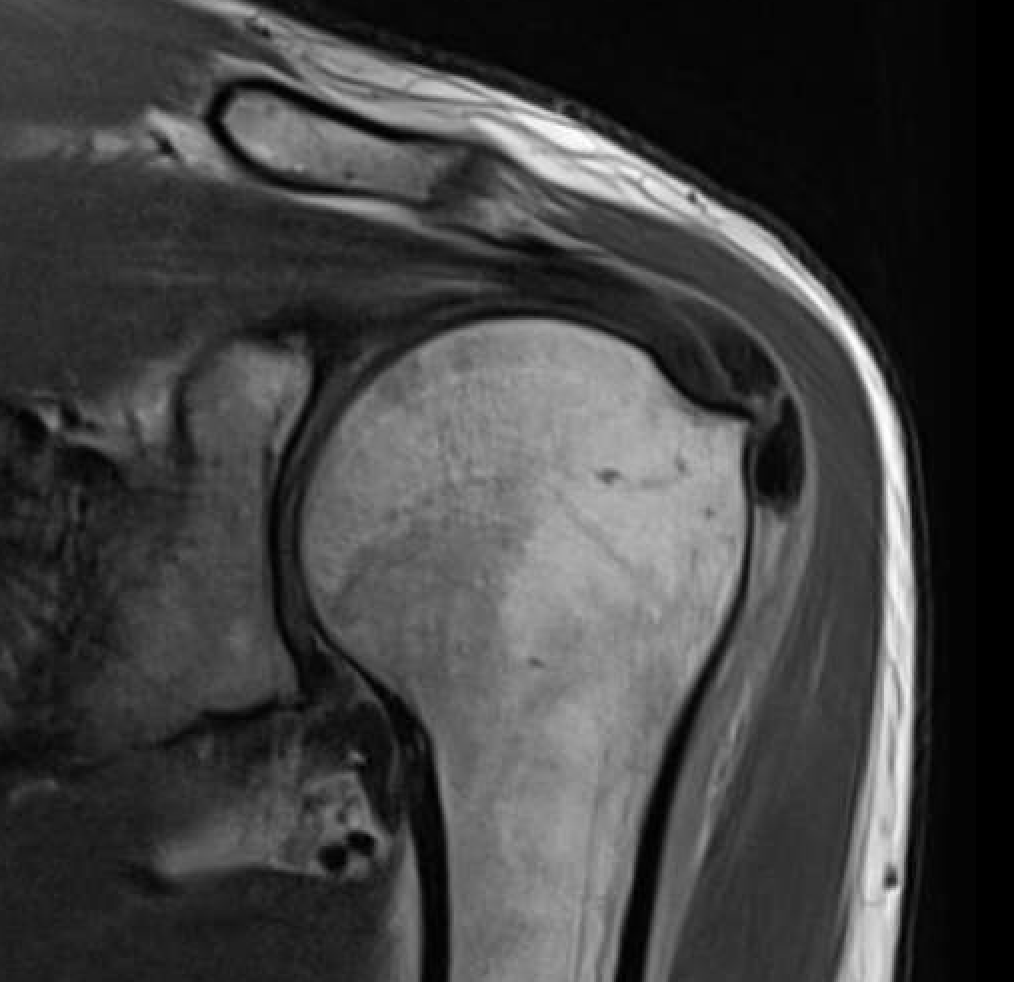

MRI

Calcium has low signal intensity on all sequences